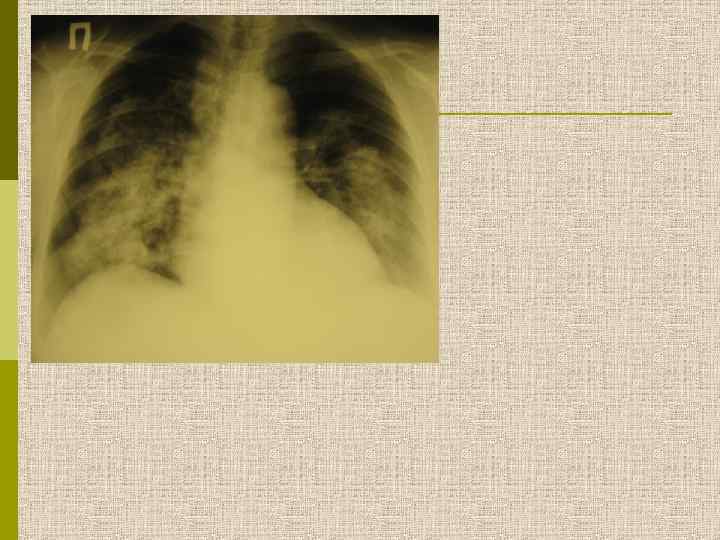

Легочные симптомы при микроскопическом полиангиите Атрофия мышц правой кисти Альвеолярная геморрагия правого легкого